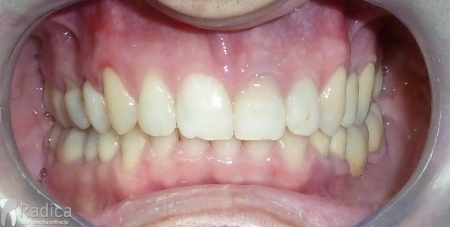

U galeriji slika su prikazani klinički slučajevi ovakvih odraslih pacijenta bilo da se radi samo o ortodontskoj terapiji ili predprotetskoj ortodonciji.

Na sljedećoj slici mogu se vidjeti početak i kraj ortodontske terapije. Pacijentica je upućena od svog stomatologa nakon što nije bila zadovoljna izgledom osmjeha i odnosom zuba i gingive u privremenom protetskom radu. Napravljena je ortodontska terapija samo u gornjoj čeljusti a nakon toga novi privremeni protetski rad.